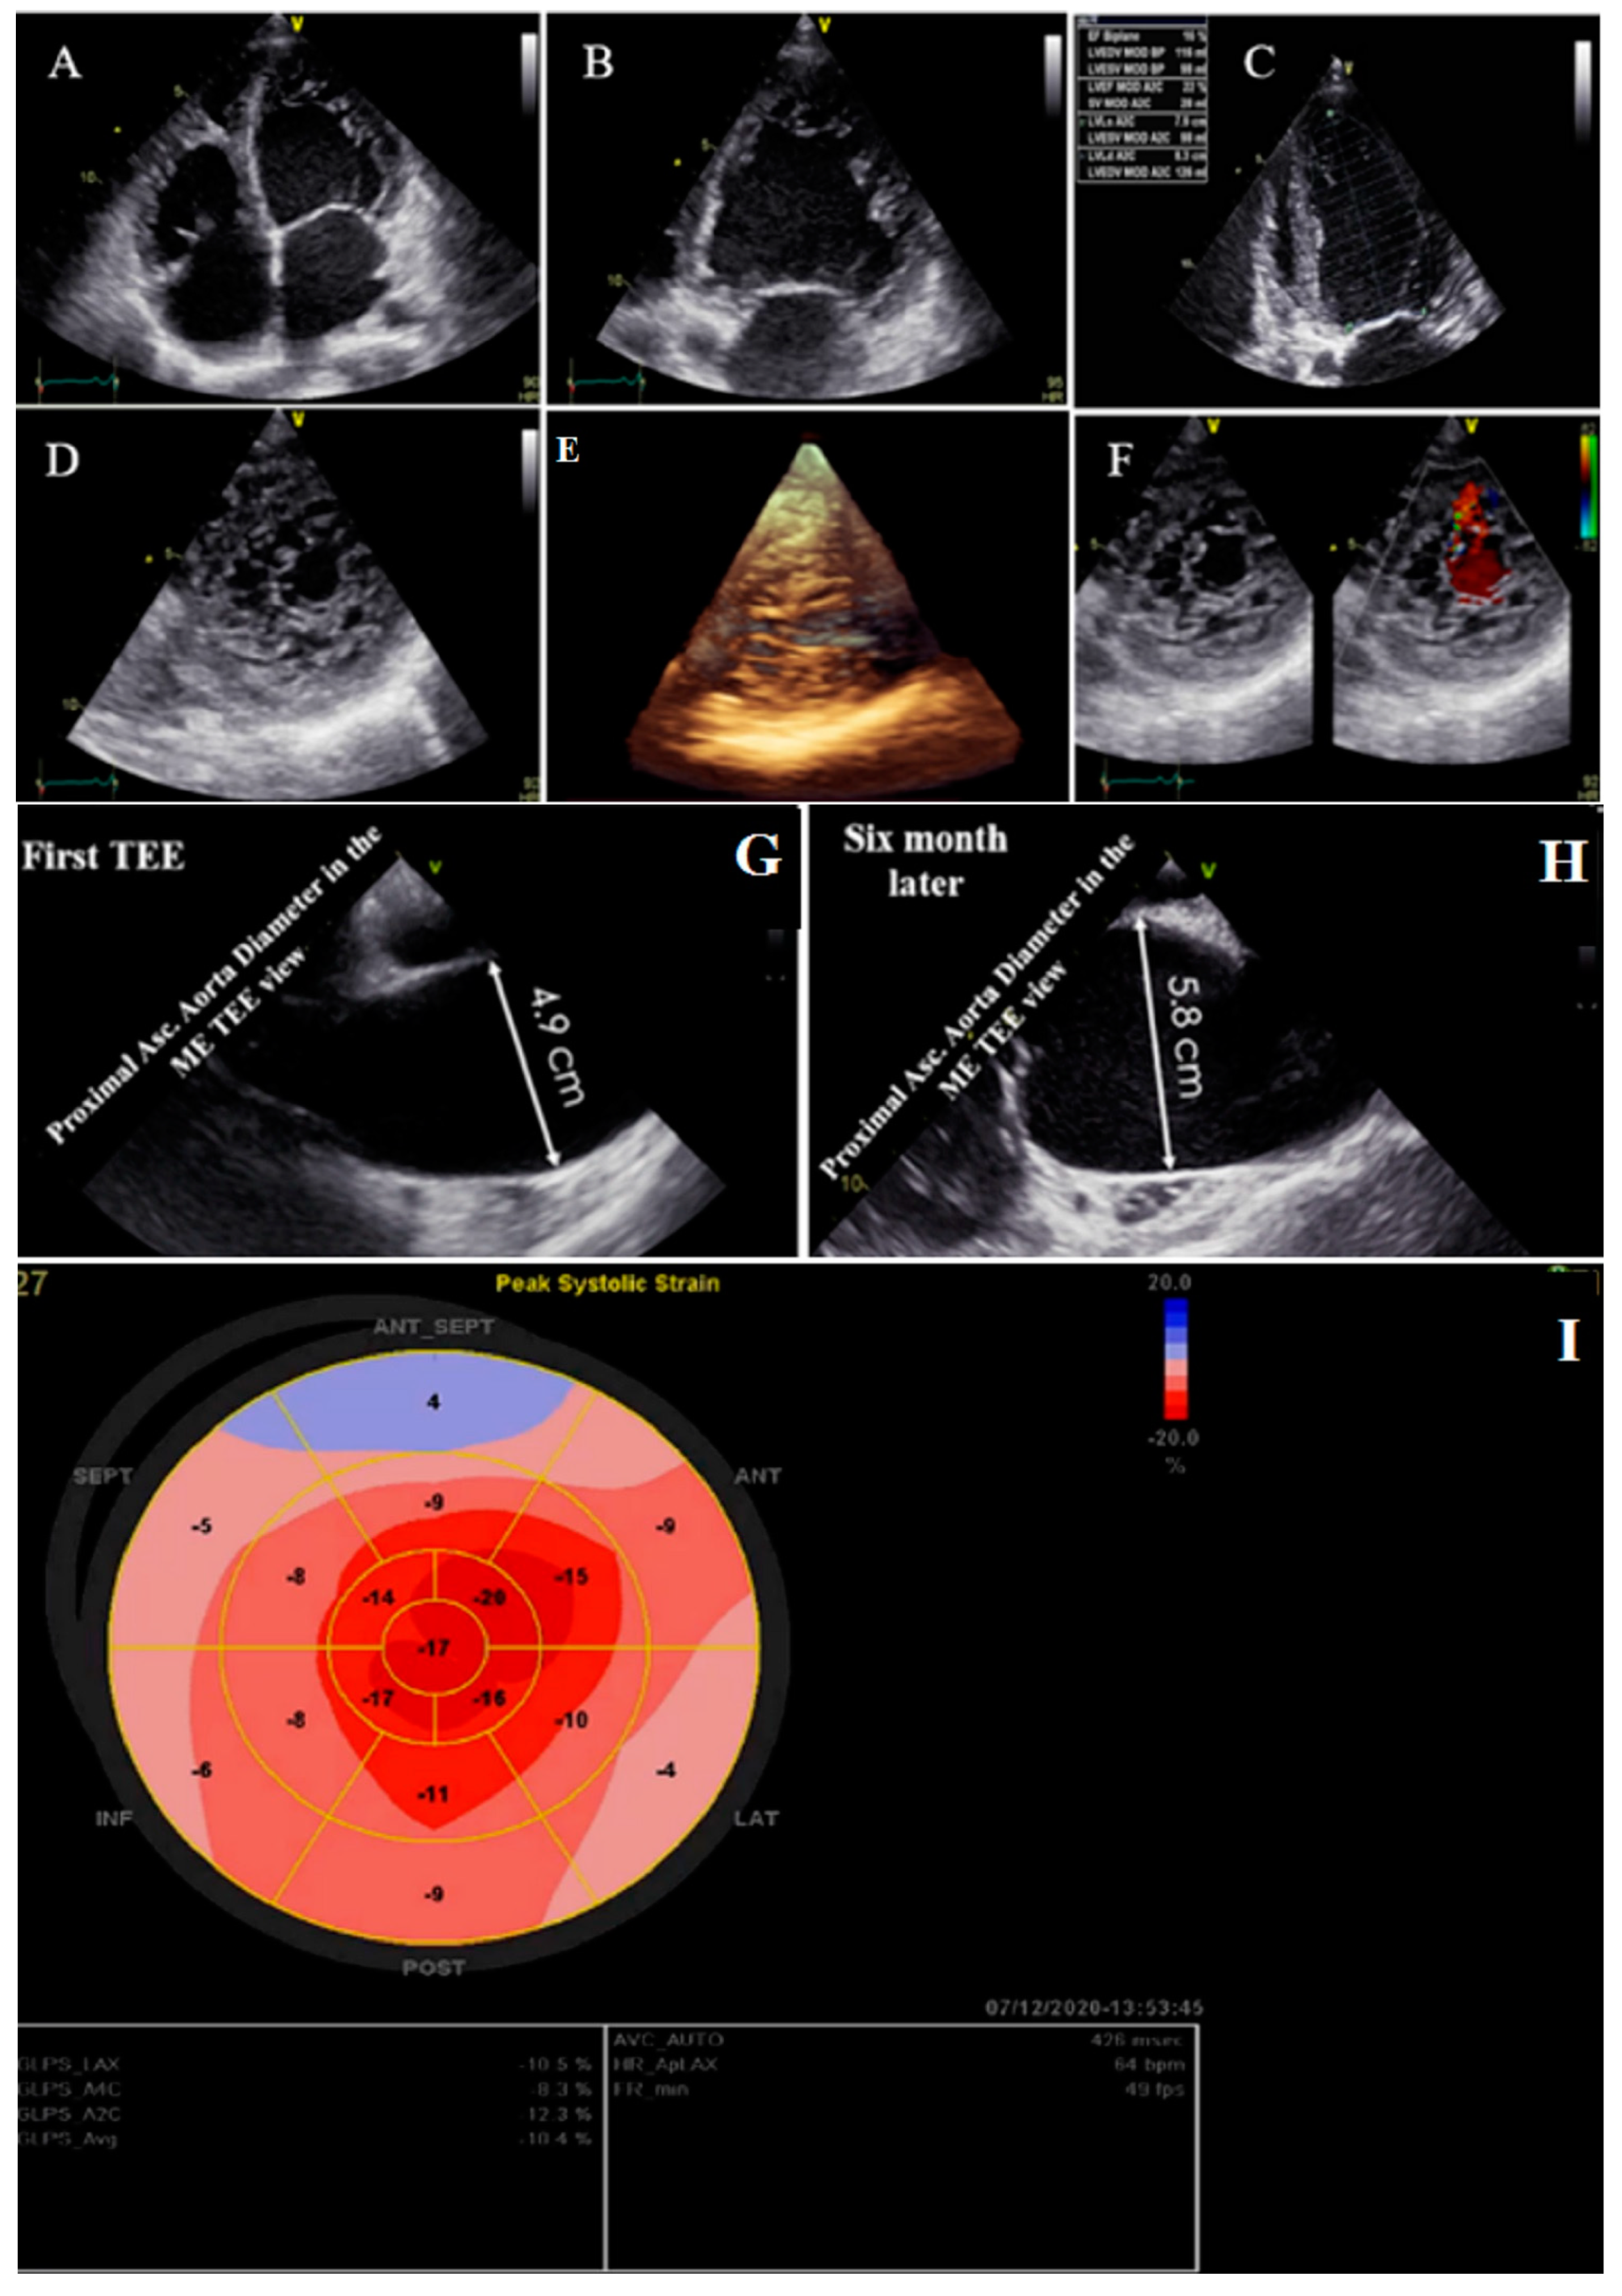

2.3. Case #3. NCLV with Aortic Dilation Complicated by Coronary Embolism

| 3 | M | 37 | Acute retrosternal pain with radiation to both shoulders since three hours prior to admission | − | NCLV, LVEF = 55% | Aortic dilation and coronary embolism | + | + | Anticoagulation plus dual antiplatelet therapy for two weeks switched to lifelong warfarin | Doing well |